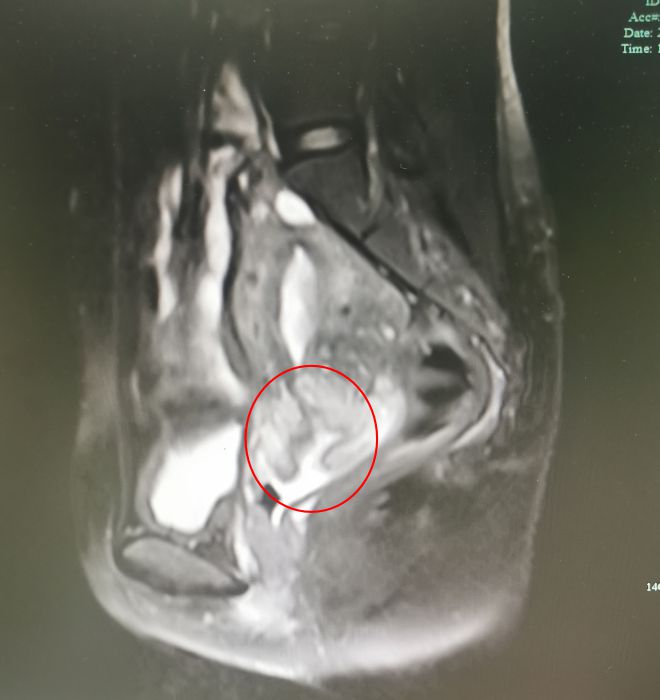

赵秀敏顺利完成了 宫腔镜下完整切除宫颈囊性腺肌瘤手术 ,术后数日杨女士复查磁共振,虽然宫颈膨大,尚未完全恢复,但包块已消失。

△术后短期复查磁共振,囊肿已消失